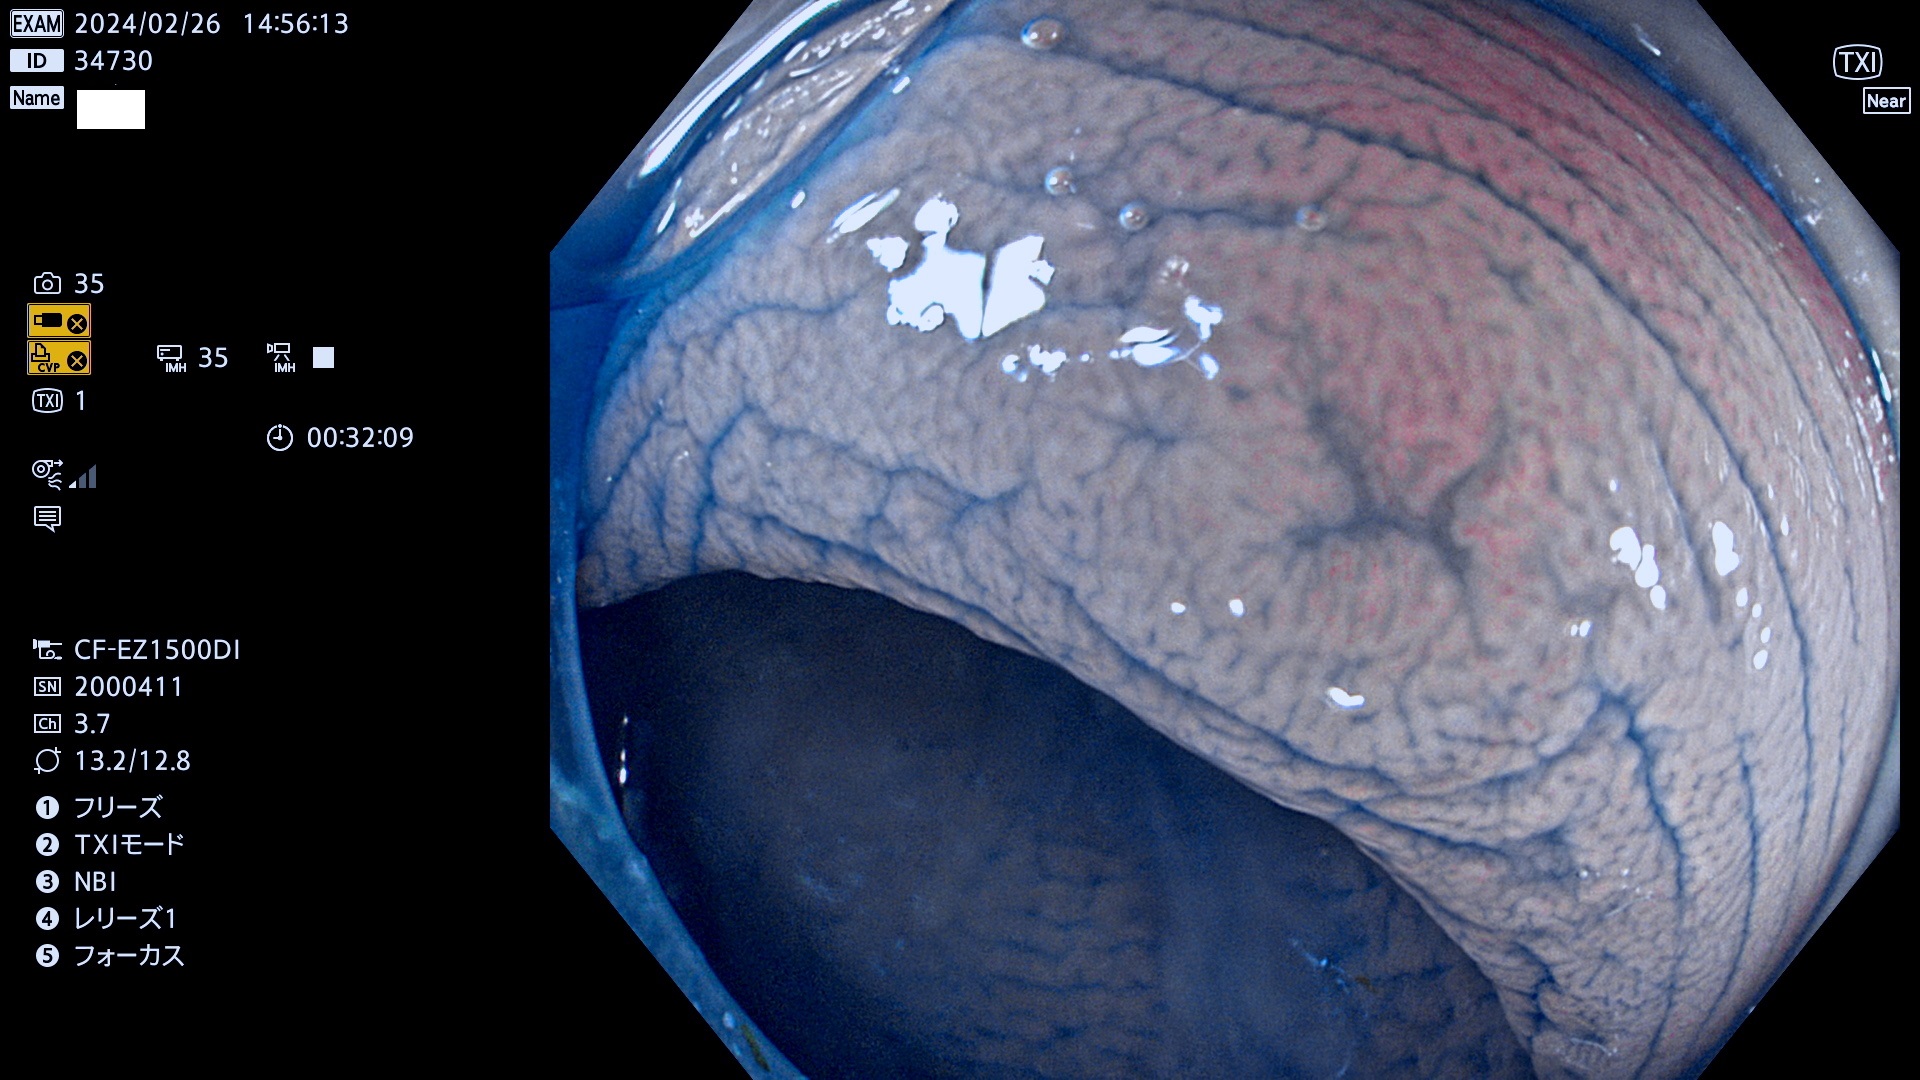

以下は当院で経験した「ビランと鑑別の難しいUc型腺腫」です(全て、病理で腺腫を確認済み)。

このような病変は表面を拡大観察しても診断は不可能であり、現在の内視鏡診断の「限界を超えた病変」と言えます。現実的な対策は「典型的なビランと異なる」と感じたら、「コールド法で積極的に切除する」ことと考えます。もちろん「結局はビランだった(不要な過剰切除だった)」ということもあります。しかしコールド法なら重篤な合併症は稀であり、医師は切除を躊躇すべきではないと考えます。